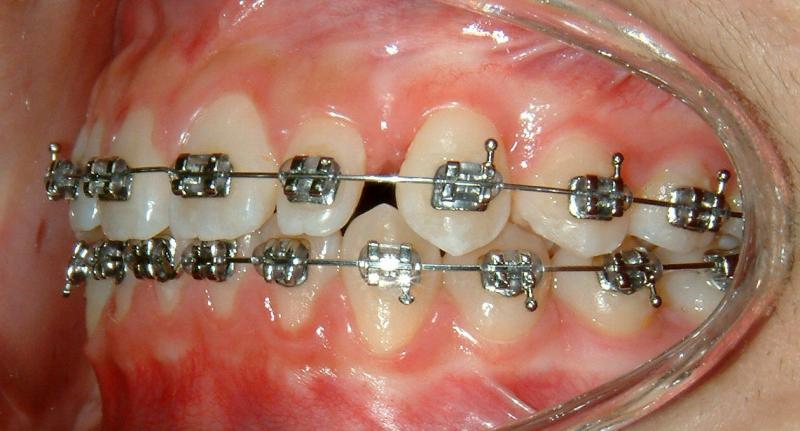

The progress of tooth eruption is complete (Fig. 24). Note that the crown of the tooth (lower left canine) is surrounded by healthy gingiva.

Fig. 24 Complete eruption, healthy gingiva, 9 months after surgical exposure (progress)